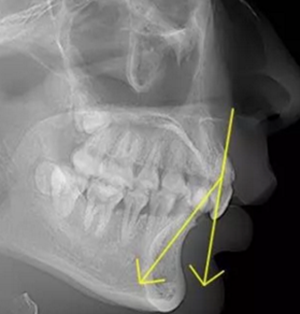

正常情況下,我們的上前牙是蓋在下前牙唇側(cè)3mm內(nèi)的,上下切牙牙軸交角為125°左右,

但前牙閉鎖合是上前牙下垂伸長(zhǎng),內(nèi)扣完全鎖住了下切牙,正面觀時(shí)我們??床坏较虑醒溃虑醒绖t常擁擠伸長(zhǎng)咬到了上腭內(nèi)的牙齦上,上下前牙發(fā)生的交角幾近180°。

正常前牙交角

前牙閉鎖合交角